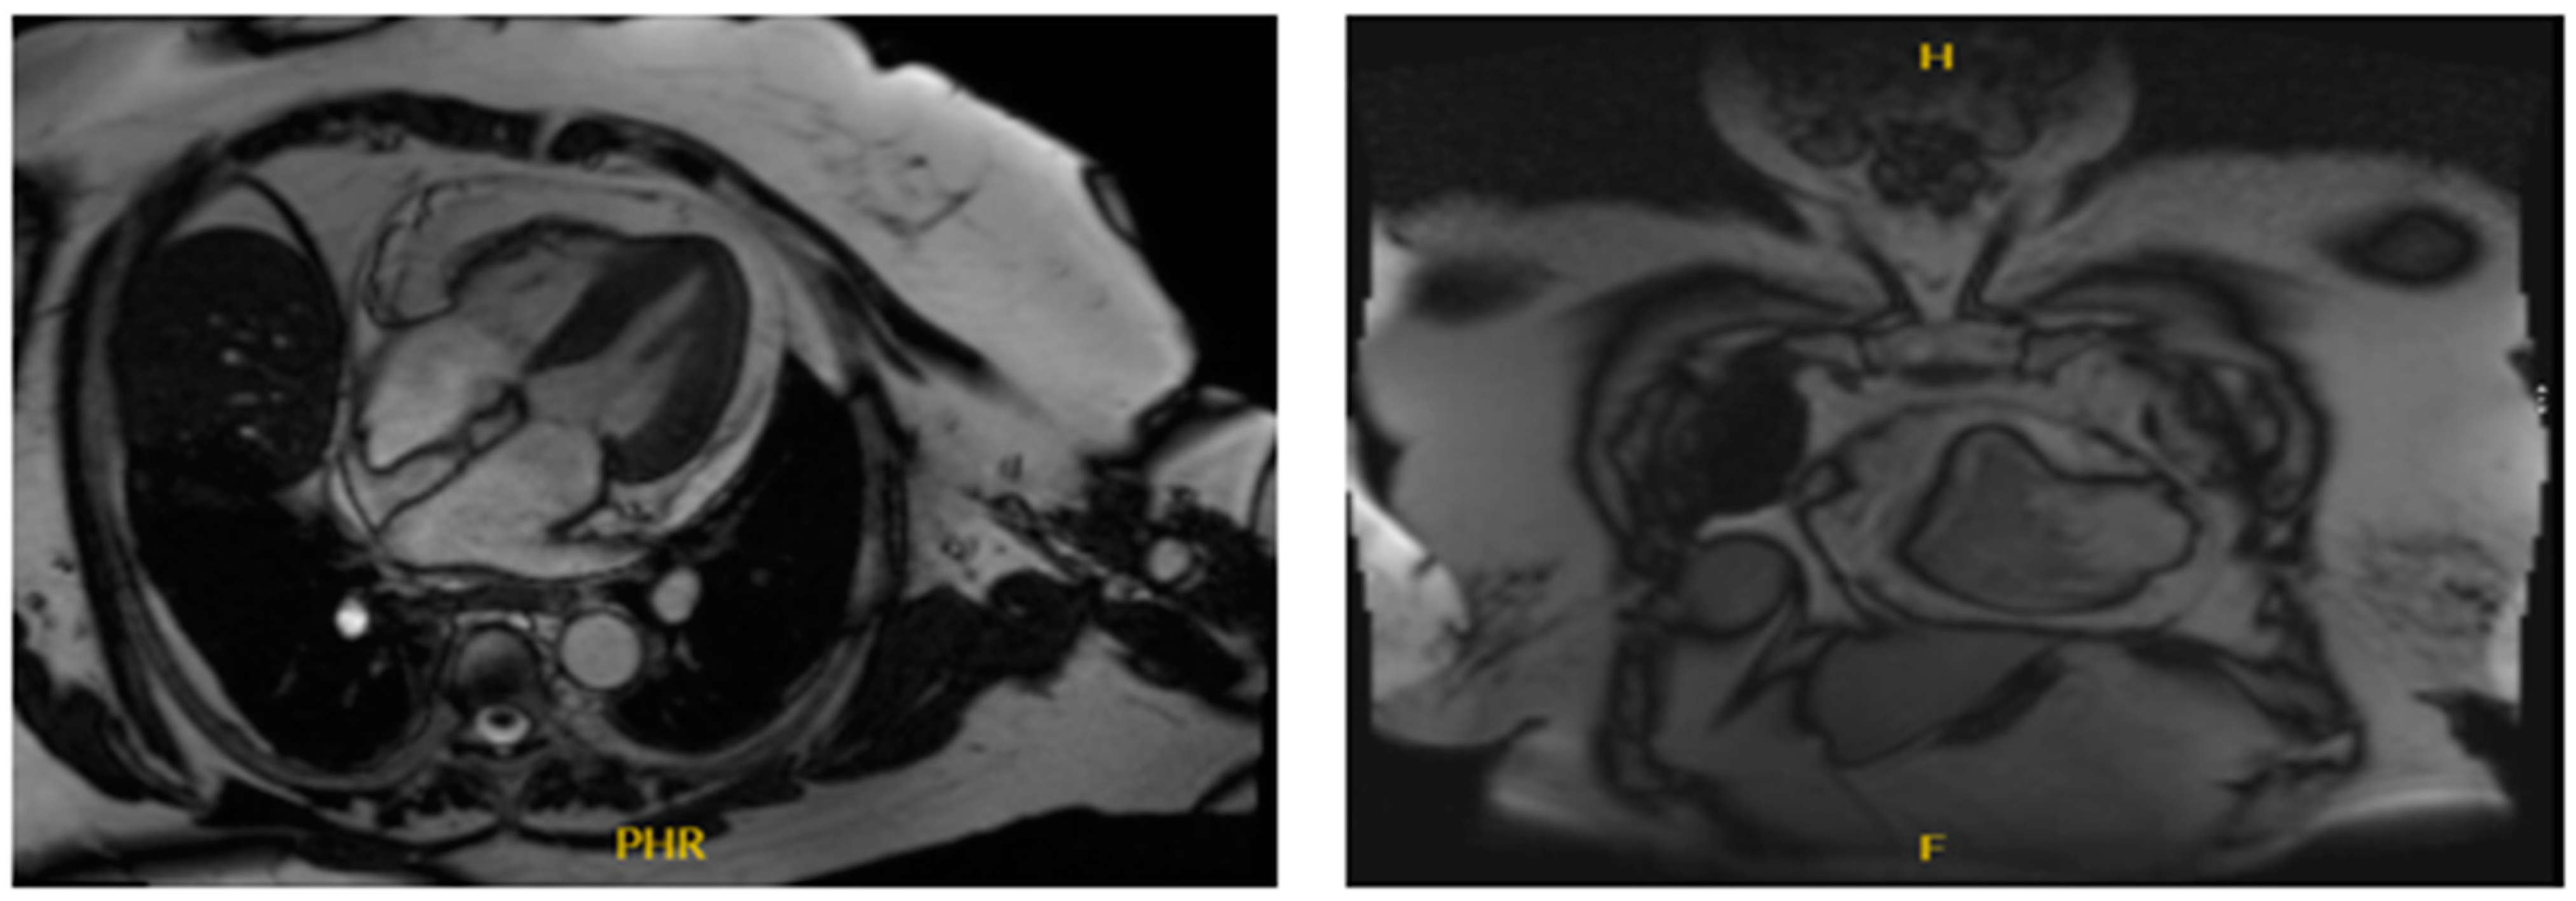

2. Case Presentation